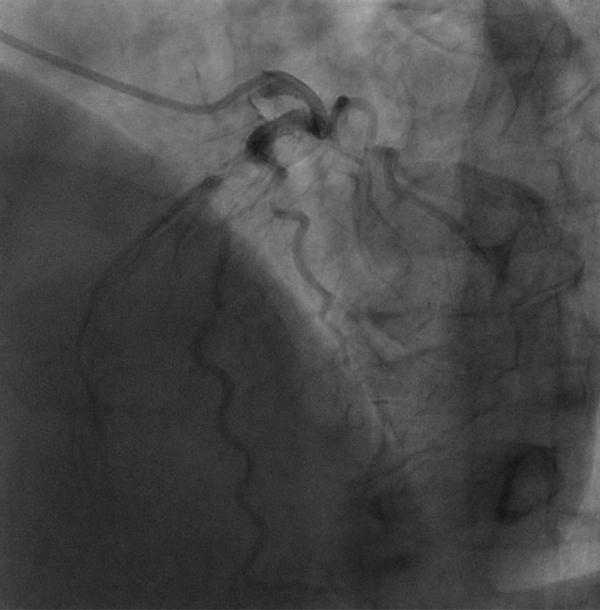

冠動脈造影で精査の結果、冠動脈で一番大切な左前下行枝の完全閉塞を認めました。

左前下行枝の完全閉塞を認めます。一枝病変であり、左胸に小開胸にてMIDCAB(左内胸動脈→左前下行枝)を施行しました。

術後の冠動脈CTにて良好な吻合形態とグラフトの開存を認めています。